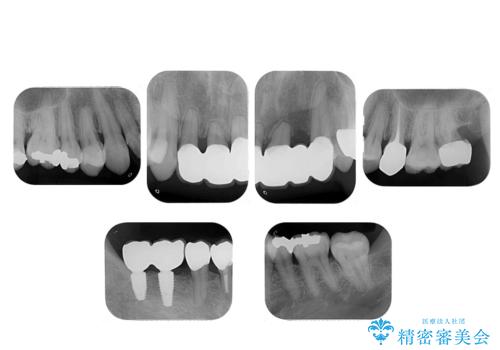

- 歯周病を気にして来院。

前歯の虫歯を治そうにも、歯並びの問題で難しい状態でした。

右下の奥歯も欠損しており、インプラント治療が必要な状態でした。

前歯の部分矯正を行い受け口を改善しました。

奥歯まで動かそうとすると顎の手術の適応になってしまうため、奥歯はそのままにして前歯のかみ合わせを改善しました。

また、奥歯はインプラント治療を行い、矯正で下の前歯を後ろに下げるのに使用しています。

前歯が重なっているところの虫歯治療が難しく、そこから矯正治療の提案となりました。

下の前歯1本、また、左上2番を保存不可能なため抜歯しています。

通常骨格的な受け口を部分矯正でというのは不可能なことが多いのですが、今回はいろいろな条件が重ねなりお引き受け可能でした。通常は難しいです。